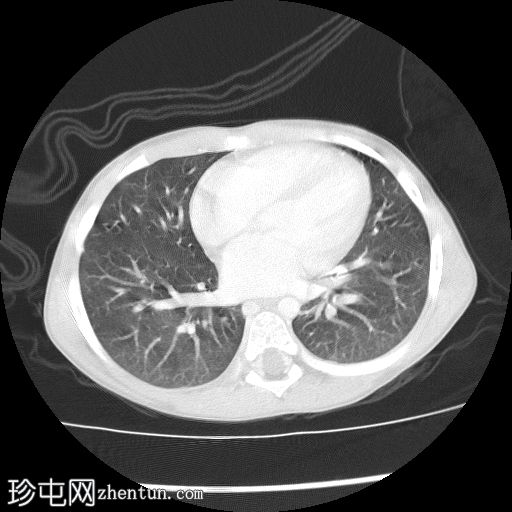

轴位

右肾向下移位至中线,呈水平位。肾上极可见一大小不一、边界相对清晰的肿块。未见明显钙化或坏死。肿块延伸至中线,但未越过主动脉/中线左侧。下腔静脉上段向前左侧移位。尽管移位,右肾静脉和动脉外观正常,未见狭窄/扩张或明显的肾静脉血栓形成。

结肠和小肠袢,尤其是在右侧腹部,向下移位,但外观无明显异常。

未见腹膜后淋巴结肿大。骨骼结构外观正常,无明显的溶骨性或成骨性改变。